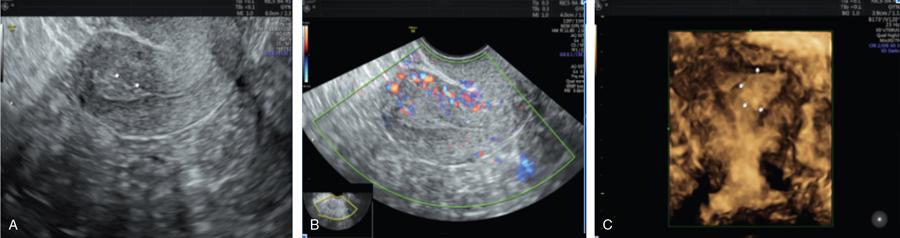

John De Lindsay, Usha Nandini Ganeshan, Vidya CERVICITIS Acute or chronic inflammation of cervix is termed as cervicitis. Noninfectious causes of cervicitis include trauma, pelvic radiation and chemical irritation. Most acute cervicitis is secondary to an infectious agent, commonly Trichomonas vaginalis, Candida albicans, herpes simplex virus, Neisseria gonorrhoeae and Chlamydia trachomatis. Patients usually present with purulent or mucopurulent cervical and vaginal discharge and may complain of pelvic pressure or discomfort. The cervix in patients with acute cervicitis shows a diffusely heterogeneous echotexture of the cervical mucosa and stroma, but the key finding is markedly increased vascularity on colour Doppler. Absence of mass is the differentiating feature between inflammation and malignancy. Free fluid can also be seen in the pouch of Douglas. CT may demonstrate an enlarged uterine cervix, an abnormally enhancing endocervical canal, and parametrial fat stranding. Retention cysts of the uterine cervix are termed as nabothian cysts. They are formed as a result of the healing process of chronic cervicitis. They are usually less than 1 cm, incidentally detected at imaging and are considered a normal finding in multiparous women. They may enlarge and become symptomatic because of mass effect, but this happens infrequently Majority of nabothian cysts, appear as small, simple anechoic cysts in the cervix, with no internal vascularity (Fig. 11.18.1.1). Their appearances can also vary depending upon any internal proteinaceous or haemorrhagic content, cyst clustering and deeper cervical stromal extension. US features that raise concern for malignancy include a solid component and marked vascular flow in the lesion at colour Doppler US. Tunnel cluster is a special variant of nabothian cyst with complex multicystic dilatation of the endocervical glands. Though macroscopically it resembles adenoma malignum, the epithelial cells of the tunnel cluster, do not show any cellular atypia similar to nabothian cyst. Nabothian cysts exhibit intermediate or slightly high signal intensity on T1-weighted (T1W) images and have prominent high signal intensity on T2-weighted (T2W) images. Presence of a solid component surrounding or separating the cysts gives us a clue to differentiate adenoma malignum from a benign nabothian cyst cluster. MR imaging also may be helpful in distinguishing adenoma malignum from benign multicystic lesions of the cervix. MR imaging features associated with malignancy include irregular margins, enhancing solid components, local invasion and metastases. CERVICAL STENOSIS Stenosis of the uterine cervix is the pathological narrowing of the cervix. The term cervical stenosis is clinically defined as cervical narrowing that prevents the insertion of a 2.5-mm-wide dilator. In utero exposure to diethylstilbestrol contributes about 20% of the cases. Often associated with endometriosis. Cervical stenosis in menopausal patient is asymptomatic. Retrograde menses may occur in women of reproductive age, thus posing a risk of endometriosis. Dysmenorrhea is present in up to 50% of patients with cervical stenosis. If the stenosis is severe enough, it may result in proximal obstruction resulting in haematometra, hydrometra, pyometra, haematosalpinges. The symptoms depend upon the severity of stenosis. Other potential consequences include infertility, impediment to assisted fertility techniques – embryo transfer and intrauterine insemination. Any pathological process that can cause inflammation of the cervical mucosa, resulting in erosion and regeneration can result in cervical stenosis. This includes: Narrowing of the endocervical canal may be observed (normal diameter: 0.5–3.0 cm). Complete obliteration of the cervical os will prevent insertion of the hysterosalpingographic catheter. The endocervix can be normal in appearance or slightly thickened. If post irradiation, the cervix may demonstrate loss of the normal zonal architecture. There may be mild to moderate fluid distension of the endometrial cavity (Fig. 11.18.2.1). If the fluid has internal echoes a careful search for potentially associated endometrial or cervical mass lesions, should be done. Complex, particulate intracavitatory fluid with its heterogeneous echogenicity at ultrasound may mimic a solid lesion; however, the absence of detectable flow at colour Doppler US and the central location should suggest the correct diagnosis. May reveal complications due to cervical stenosis such as hydrometra and haematometra and haematosalpinges. Though the cervix may be appear normal, the uterine cavity may be fluid filled. Auxiliary findings may suggest an underlying cause, such as an obstructive mass lesion, or post radiation bowel wall thickening. In equivocal cases, MR imaging may be useful to differentiate complex endocervical fluid from a mass. In selected situations, gradual dilatation of the cervix under ultrasound guidance, can be an effective treatment. Depending on severity of disease, other treatment options include insertion of laminaria tent, hysteroscopic cervical excision or in extreme cases total hysterectomy. CERVICAL POLYPS The common cervical polyps are prolapsing endometrial polyps. They are seen in endocervial canal. Endometrial polyps are common and a frequent cause of abnormal uterine bleeding. They account for approximately 30% of cases of postmenopausal bleeding. In menstruating females, they may cause intermenstrual bleeding, metrorrhagia, and infertility. Polyps can be histologically characterized as localized hyperplastic overgrowths of glands and stroma covered by epithelium. The typical appearance of an endometrial polyp at sonography is a well-defined, homogeneous, polypoid lesion that is isoechoic to hyperechoic to the endometrium with preservation of the endomyometrial interface (Fig. 11.18.3.1). There usually is a well-defined vascular pedicle within the stalk demonstrated on colour Doppler sonography (Fig. 11.18.3.2). Uncommon features of polyps include multiplicity, cystic components, a broad base and hypoechogenicity or heterogeneity. Occasionally, polyps can have a heterogeneous echotexture with multiple cysts. This complex appearance may be due to haemorrhage, infarction or inflammation within the polyp. Sonohysterography is an ultrasound technique in which the endometrial cavity is distended with saline allows evaluation of single layer of the endometrial lining and enables us to reliably distinguish focal from diffuse endometrial pathologic conditions. Focal lesions are defined as lesions occupying less than 25% of the endometrial surface area and diffuse lesions involve a larger percentage of the endometrial surface area. Saline infusion sonohysterography which involves the infusion of fluid to visualize the endometrium is a simple, well-tolerated and inexpensive procedure. Sonohysterography is best performed as soon as possible after the bleeding cycle has ended when the endometrium is thin. When the patient has irregular bleeding, that she cannot tell what is actual menses, in such cases it may be helpful to use an empiric course of a progestogen such as medroxyprogesterone acetate 10 mg daily for 10 days as a medical curettage and then time the ultrasound examination to the withdrawal bleed. The decision about whether to obtain cultures and use of antibiotics depends very much on the patient population with which the physician deals with. Anaesthesia or analgesia is not required. A bimanual examination to know the version of the uterus is done. The vaginal speculum is inserted. Under sterile aseptic precautions, a catheter is inserted into the cervix. This is done by grasping the cervix with a ring forceps feeding it through the os. A cervical stabilizer may be used and it will be less painful, less traumatic and does not cause bleeding from the cervix. The speculum is removed without dislodging the catheter. The vaginal probe is then reinserted. A 10-mL syringe is attached to catheter. Scanning in long-axis projection, fluid is instilled while watching the video monitor. In that long-axis projection the transducer is removed from side to side (i.e. from cornua to cornua). The amount of fluid instilled is variable and depends on the image which is producing on the ultrasound screen. When the uterus has been completely rotated 90 degrees into a coronal plane further fluid is instilled, while fanning down toward the endocervical canal and up toward the uterine fundus. Very minimal fluid acts as a sufficient interface to distinguish anterior and posterior endometrial surfaces and outline endometrial pathology. The risk of malignant cell dissemination exists but is small. The saline infusion sonohysterography can reliably distinguish dysfunctional abnormal bleeding (no anatomic abnormality) from those with globally thickened endometrium. Endometrial polyp appears as homogeneous, well-circumscribed, polypoid lesion that is isoechoic to the endometrium with preservation of endometrial–myometrial interface. Other features can be cystic components, multiplicity, a broad base, and hypoechogenicity or heterogeneity. Submucosal leiomyomas are usually broad-based, hypoechoic, well-defined, solid masses with shadowing and an overlying layer of echogenic endometrium that distorts the endometrial–myometrial interface. They are pedunculated or have a multilobulated surface. The major advantage of sonohysterography is the accuracy in depicting the percentage of the fibroid that projects into the endometrial cavity. In contrast to the transvaginal US demonstration of polyps, which may distort measurements of endometrial thickness if made before saline infusion, at sonohysterography the uninvolved single-layer endometrium appears normal in thickness and should be measured separately from the polyp. The findings at sonohysterography determine whether a blind biopsy, hysteroscopically guided biopsy, or hysteroscopically guided dilation and curettage is the appropriate diagnostic. On MRI polyps appear T2 isointense to hypointense and demonstrate postcontrast enhancement (Fig. 11.18.3.3). Polyps generally enhance less than the surrounding endometrium but more than myometrium. Most of endometrial polyps can be reliably differentiated from submucosal leiomyomas on MR imaging with leiomyomas having hypointense signal on T2W and visualizing origin from the myometrium. A small percentage of endometrial polyps may contain malignant foci or foci of endometrial hyperplasia. Hormones (endogenous or exogenous), tamoxifen usage, nulliparity, obesity, hypertension and diabetes. Histologic patterns of endometrial hyperplasia vary from hyperplasia without atypia, which has little or no malignant potential, to severe atypia in which 20% of cases progress to endometrial cancer. Endometrial hyperplasia accounts for approximately 4%–8% of cases of postmenopausal bleeding. In sonohysterography, endometrial hyperplasia appears as a diffuse thickening of echogenic endometrial stripe without focal abnormality, uncommonly focal endometrial hyperplasia can be seen. In sonohysterography the latter form of hyperplasia is more difficult to differentiate from endometrial polyps because characteristics of the focal endometrial thickening in both conditions overlap. Endometrial cancer is typically a diffuse process, but early cases can appear as a polypoid mass. Imaging features of endometrial hyperplasia include irregular thickening of the endometrium with T2 hyperintensity compared to normal myometrium and T1 hypointensity relative to myometrium on early contrast-enhanced images. Endometrial thickening measuring >5 mm in postmenopausal females with bleeding, regardless of hormonal therapy should undergo further investigation including tissue sampling to exclude endometrial cancer. Cervical polyps are the commonest causes of intermenstrual vaginal bleeding. Most patients are perimenopausal present with symptoms including menorrhagia, postmenopausal bleeding, contact bleeding and vaginal discharge. Pathologic conditions of cervical polypoid lesions include endometrial or endocervical tissue with metaplasia, leiomyoma, inflammation or malignancy or even blood clot. Most common are endocervical polyp, account for more than 60% of cervical polypoid lesions. More commonly polyps are pedunculated, with a slender pedicle of varying length, but few are sessile. The diagnosis is made primarily with hysteroscopy. Endocervical polyps are usually seen as masses with or without cysts filling endocervical or vaginal canal. Identifying the stalk attaching to the cervical wall may differentiate it from endometrial polyp. On USG it appears hypoechoic or echogenic with a stalk. CERVICAL CARCINOMA Cervical carcinoma is the third most common gynaecological malignancy after endometrial and ovarian malignancies. It affects middle-aged females from 35 to 50 years with an average age of onset at around 45 years. It is one of the leading causes of deaths among women in developing countries. Prognosis depends on tumour size, nodal status, histological grading and staging at the time of diagnosis. So accurate staging of the disease is very important to decide the treatment strategy.